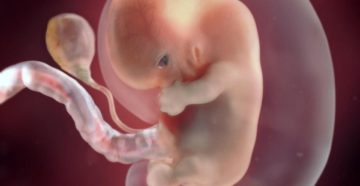

Особенности развития ребенка в возрасте восьми недель На 8-й неделе жизни малыша уже можно наблюдать…

ребенок на 9 неделе беременности нет сердцебиение Беременность – это время интенсивных изменений в организме…